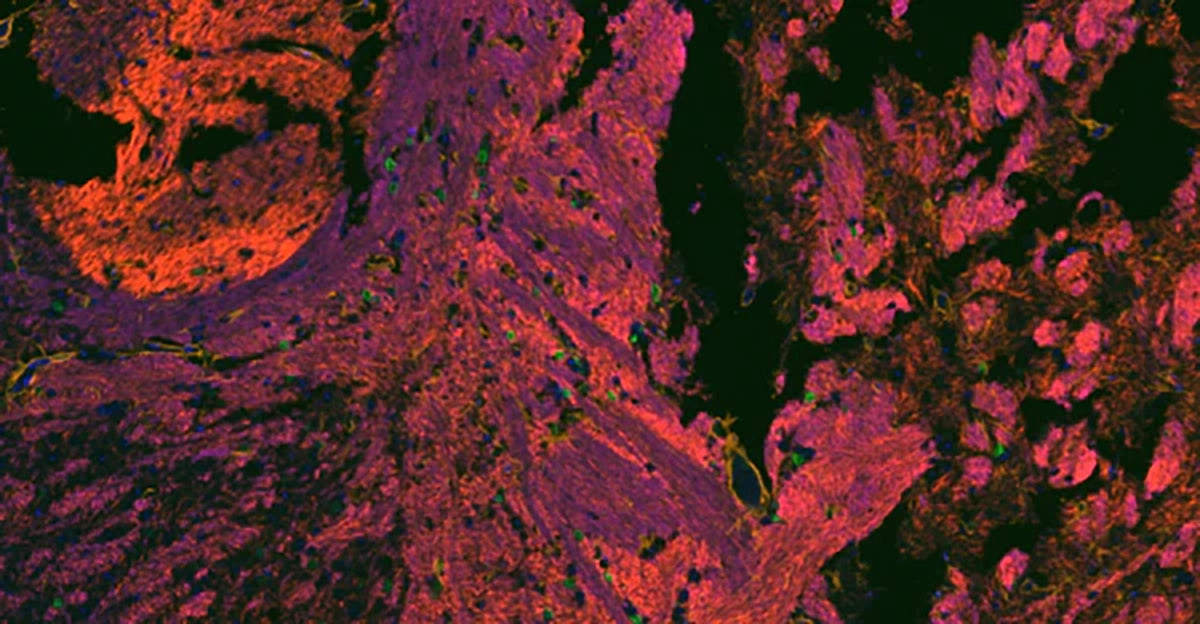

HRP Polymer Ready-To-Use Kits

The provided HRP polymer conjugated secondary antibody significantly address the limitations commonly experienced with traditional immunohistochemistry (IHC) methods, such as poor or inconsistent antigen staining when identifying low-abundance antigens or in situations of suboptimal antibody-antigen binding.

By utilizing an HRP polymer conjugate, the sensitivity of detection is dramatically increased and the process is simplified.Moreover, the HRP polymer-based amplification method reduces the amount of primary antibody needed and shortens the secondary antibodies’ incubation period.